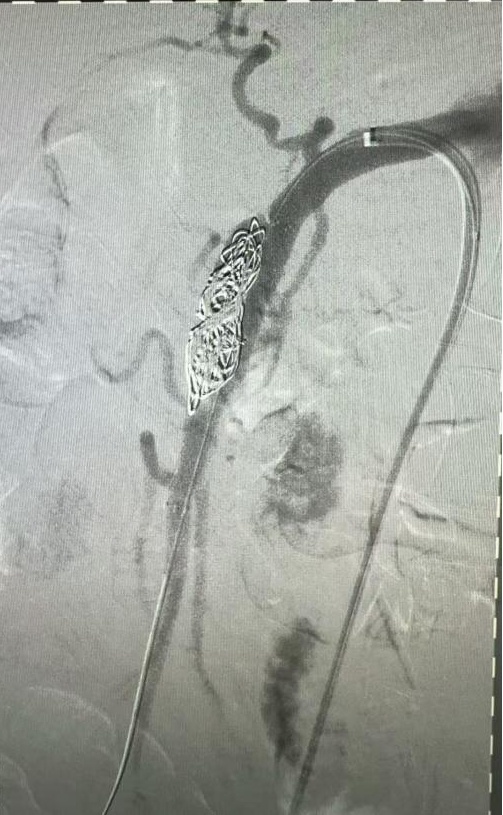

19:30,龚淞楠医生陪同患者及家属抵达嘉定院区急诊,并顺利完成交接。患者当时整体病情稳定,当晚入住血管外科,接受进一步评估和治疗。在排除相关禁忌后,11月4日,血管外科孙羽东副主任医师为患者实施了肠系膜上动脉夹层腔内隔绝+假腔栓塞术。

手术顺利完成。三天后,钱先生顺利出院。